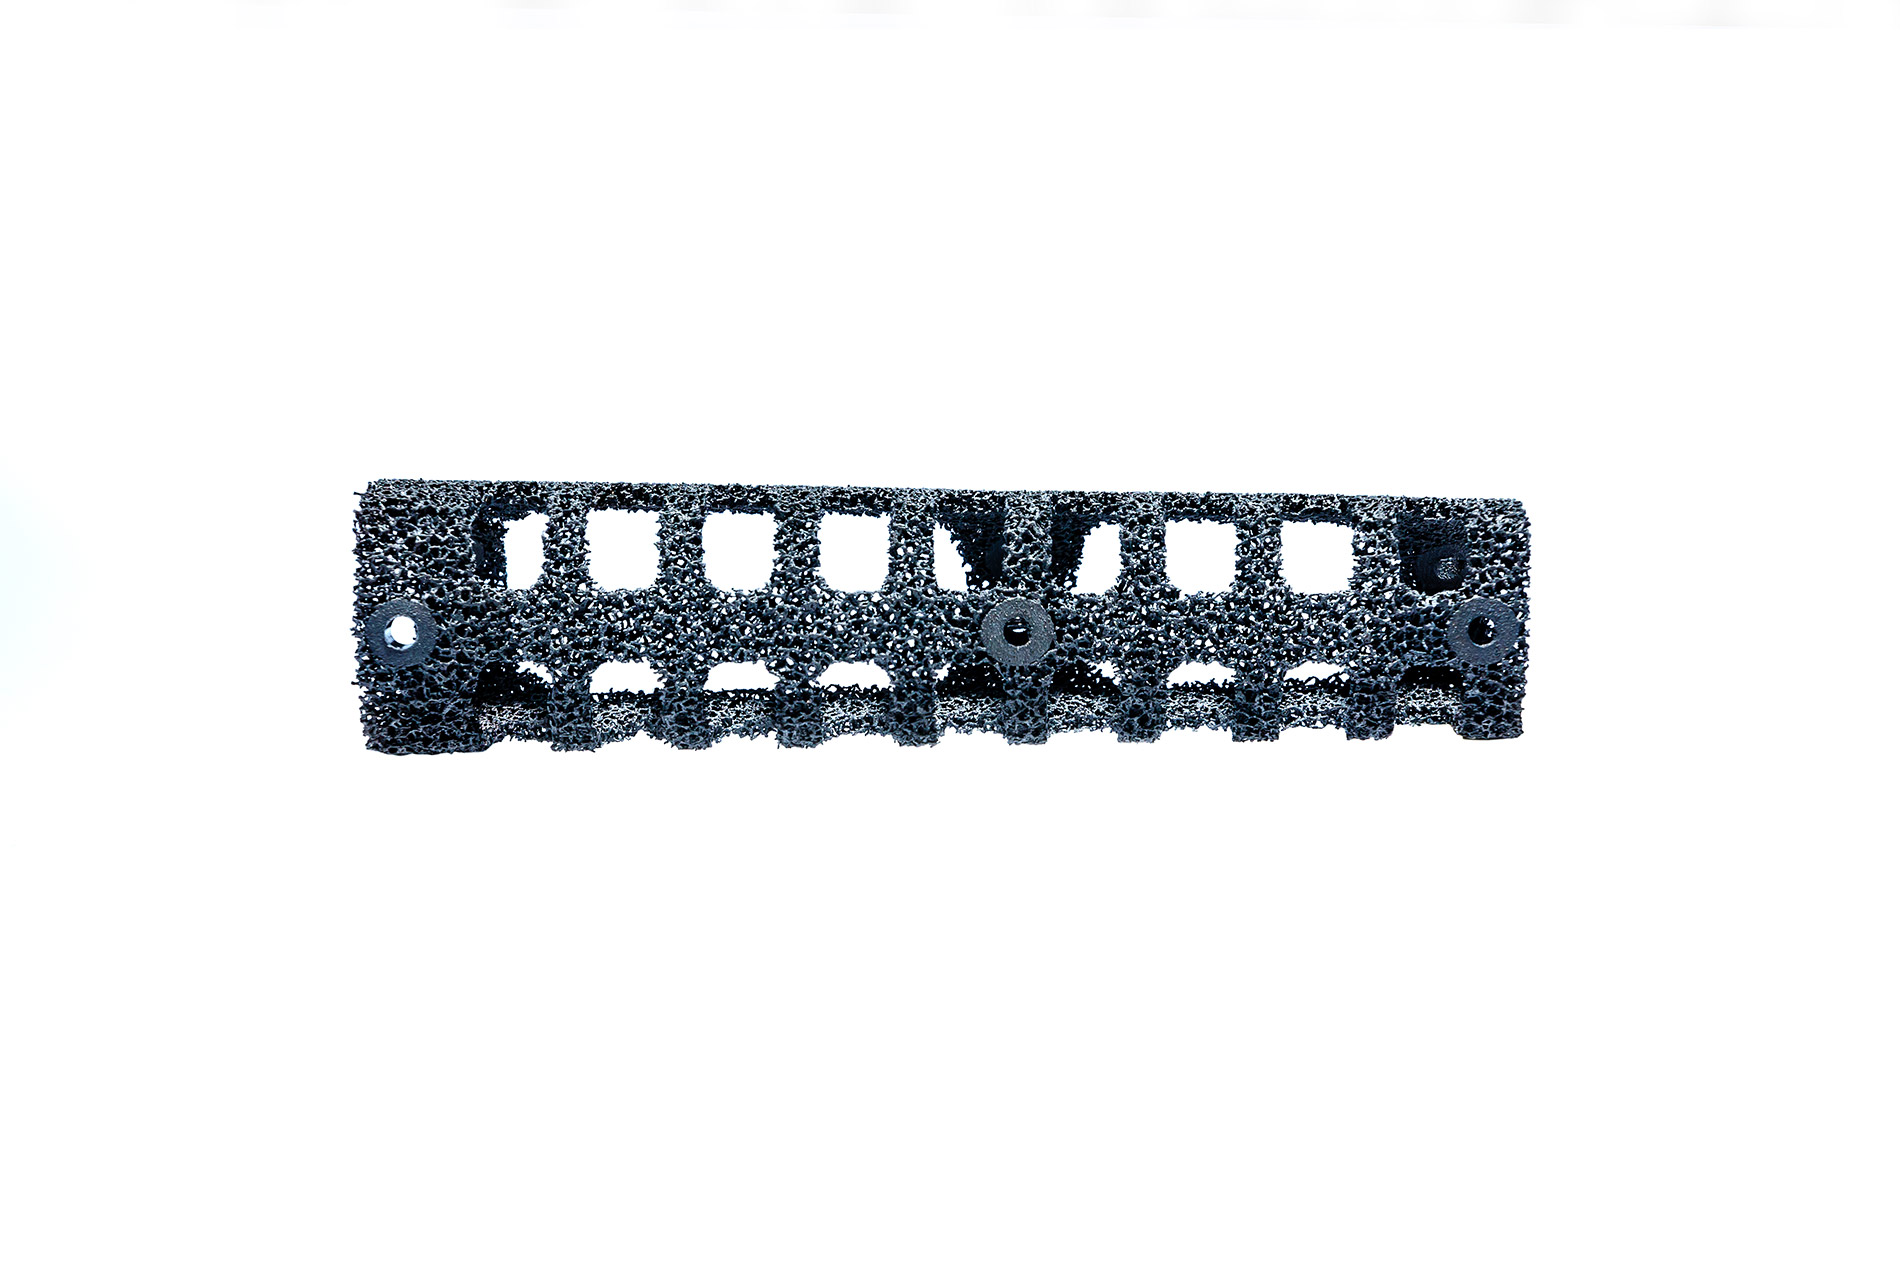

Reproducimos en nuestros implantes de titanio biocompatible la misma trama de cavidades que poseen los huesos del cuerpo humano haciéndolos livianos y extremadamente resistentes

Implantes a medida, impresos en 3D con tecnología TST® (Titanio Trabecular)